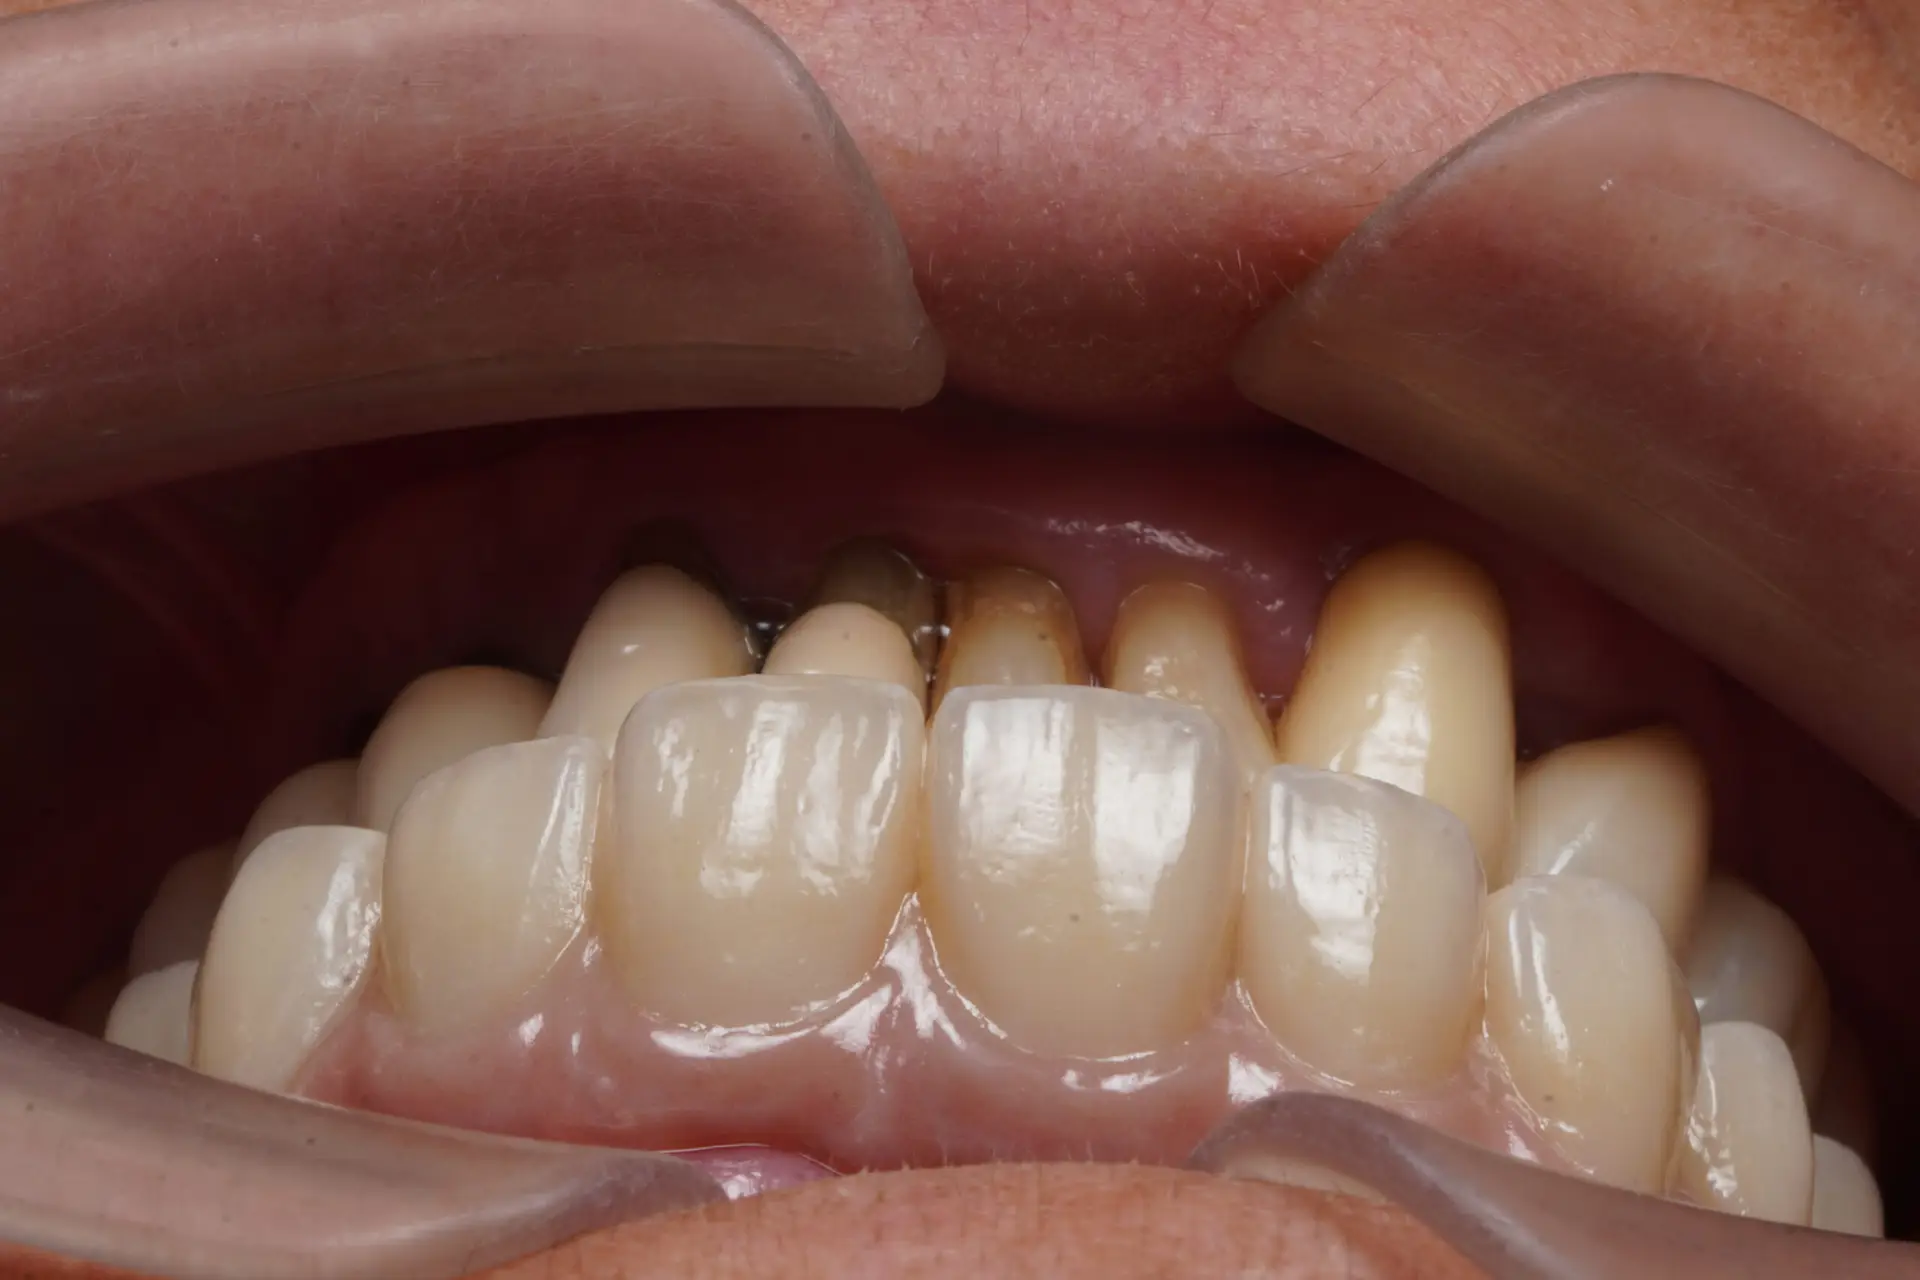

全口重建改善臉型

這位阿姨前來求診的時候,活動假牙已經不堪使用,而且頻繁出現疼痛,難以進食。 口腔中的牙齒都已經移位,而且上下難以穩定的對合,屬於咬合喪失的治療類型。 經歷了半年多的手術、臨時假牙調整,最終才確定製作全…